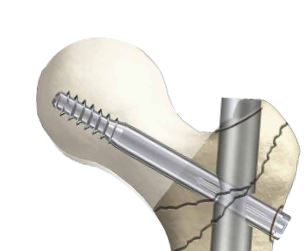

LAG SCREW, stainless steel, Ø 10.5 x 95 mm, sterile

STRY40600095S

60210

HS Code:

902110

-X SSTR40600095S